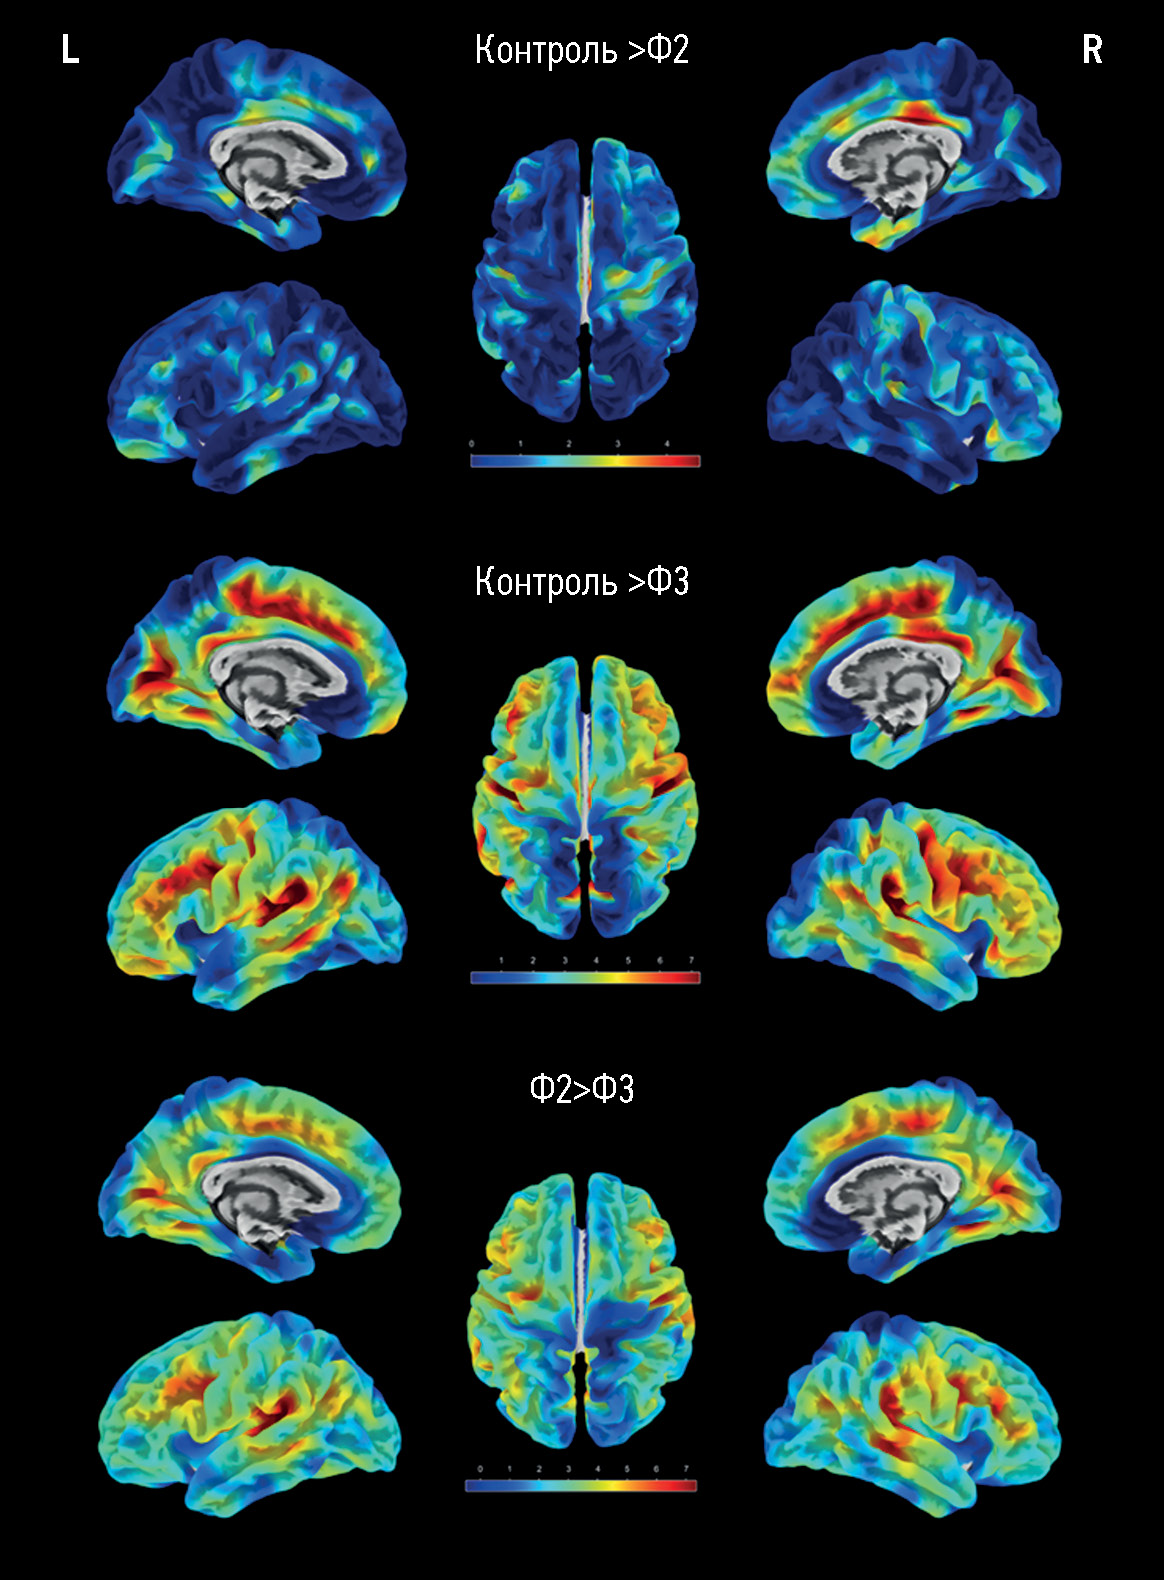

RESULTS: The main group consisted of 173 patients with cerebral small vessel disease, whereas the control group included 47 healthy volunteers. As the severity of brain structural changes and cognitive impairments increased, a significant (p <0.05) decrease in the cortical thickness of certain regions following a similar pattern was reported, particularly in the cingulate gyri, mainly their posterior sections; medial and middle sections of the frontal lobes, various areas of the insular cortex, and temporoparietal areas, particularly the supramarginal gyri. The brain volumes (overall, gray matter, and white matter volumes) in cerebral small vessel disease were significantly different only in controls but not between patients with cognitive impairment of different severity levels. The hyperintense white matter volume was significantly different between patients with dementia and moderate cognitive impairment, dementia, and subjective cognitive impairment (p <0.0001).